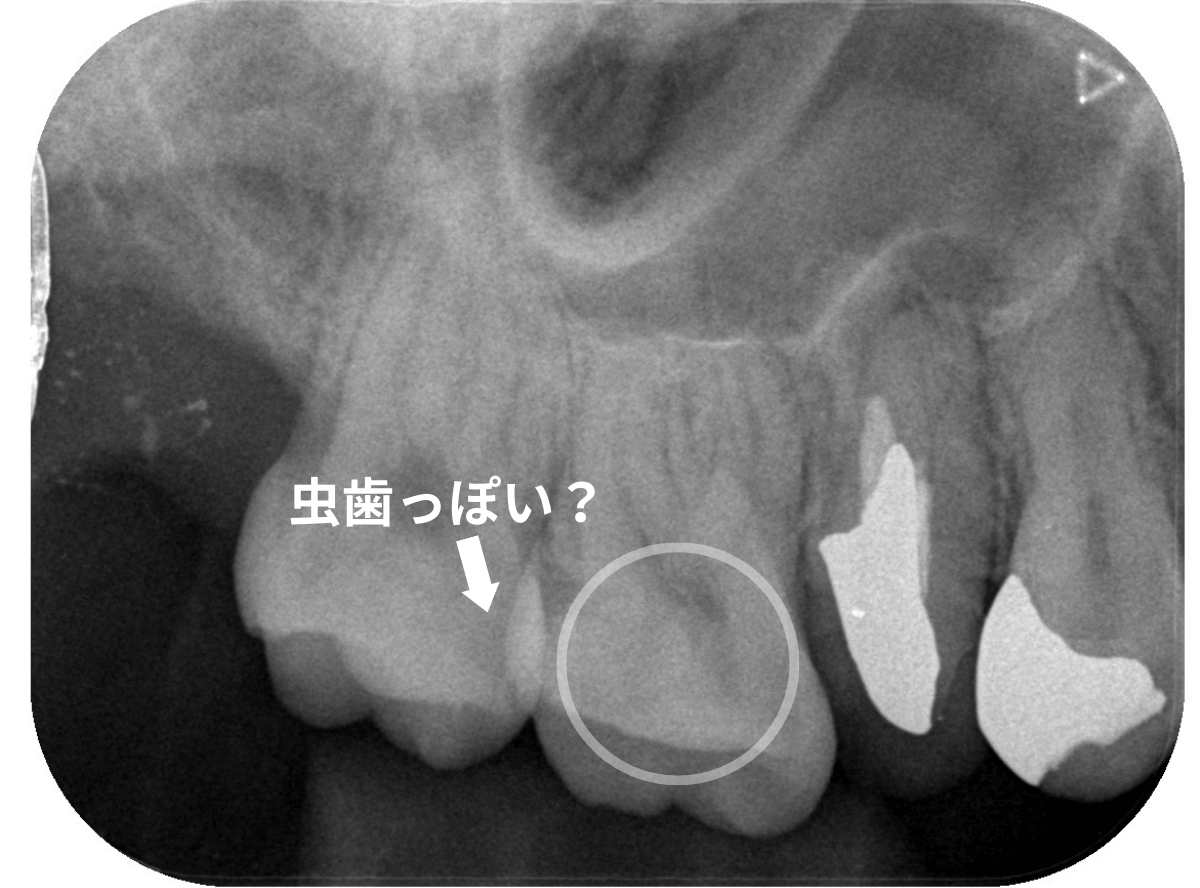

Case.18 虫歯なのは間違いないが、境界がはっきりしない

レントゲン写真で確認します。

〇部が当該の歯です。

症状もあるので、虫歯が深そうですが、全体がもやっとして、どこからどこまで虫歯なのかはっきりわかりません。

まれに、こんな時もあります。